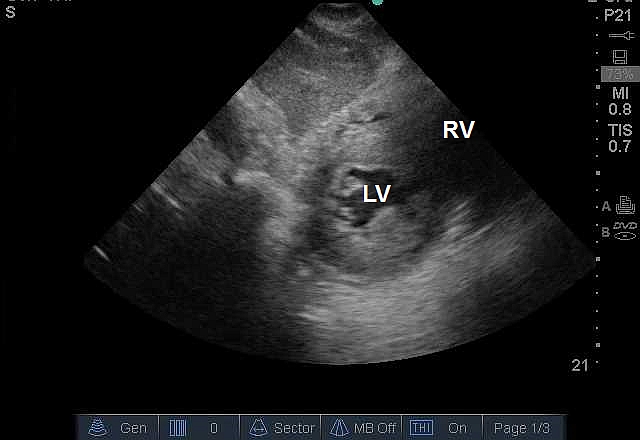

Case 7-2. Parasternal Short-axis View at the Midventricular Level

Video 7-2A. Left ventricular (LV) function is normal. The right ventricle is normal in size and there is no septal dyskinesia.

Video 7-2B. Normal LV function but with increased LV wall thickness. There is also a circumferential pericardial effusion. Strictly speaking, ventricular hypertrophy requires a formal measurement of ventricular muscle mass that requires a series of specific measurements that are not within the purview of basic critical care echocardiography. The intensivist should report increased wall thickness consistent with ventricular hypertrophy, and consider alternative causes for increased wall thickness. In this case, the patient had advanced amyloidosis.

Video 7-2C Severe LV dysfunction with segmental wall abnormality. The anterior mid septum is akinetic while the inferior and lateral walls are contracting although to reduced extent. The anterior and anterolateral walls are not well visualized due to a rib shadow. Adequate image quality in all views is frequently not possible in the critically ill. The subcostal short-axis view would be an alternative.

Video 7-2D. Severe LV dysfunction with a segmental wall pattern. The septal function is very reduced as is the anterior wall, suggesting a left anterior wall infarction, while the inferior, infero lateral, and anterolateral segments are reduced in function but to lesser extent. There is a pleural effusion with atelectatic lung within it. At the end of the clip, the tomographic plane changes to the mitral level. This resulted from respiratory translation movement of the heart, which is a common artifact of echocardiography performed in the patient with respiratory distress.